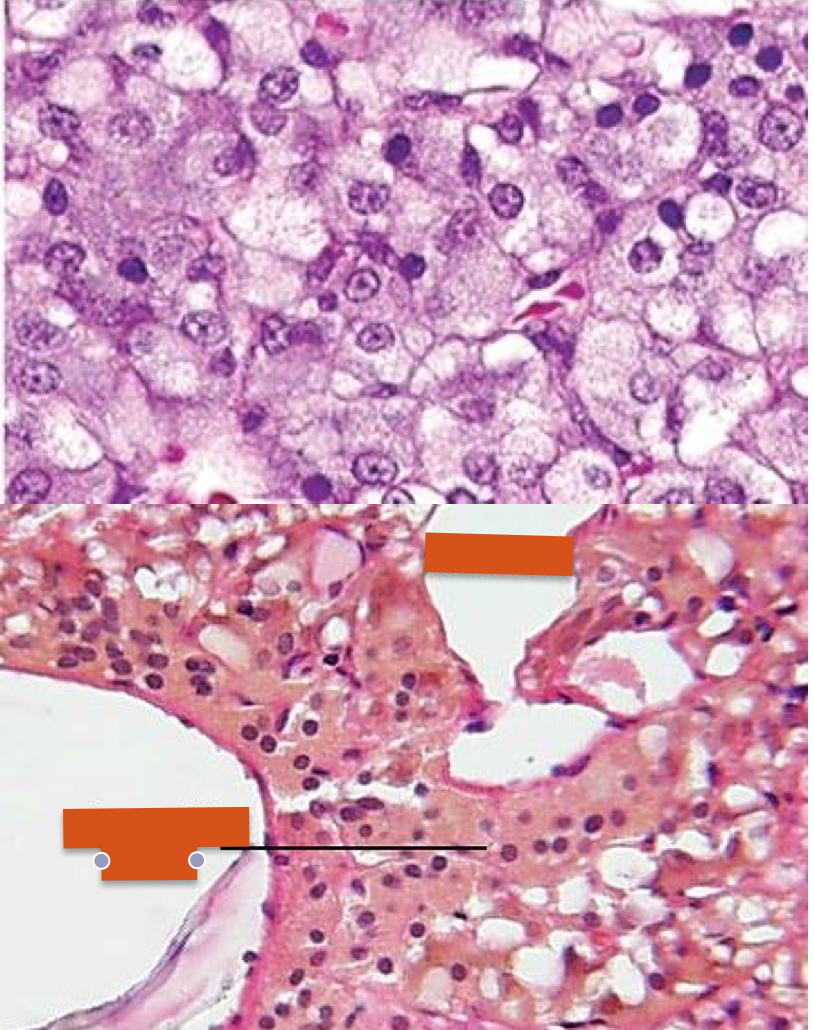

thyroid gland

***follicular cells also known as principal cells

parathyroid gland